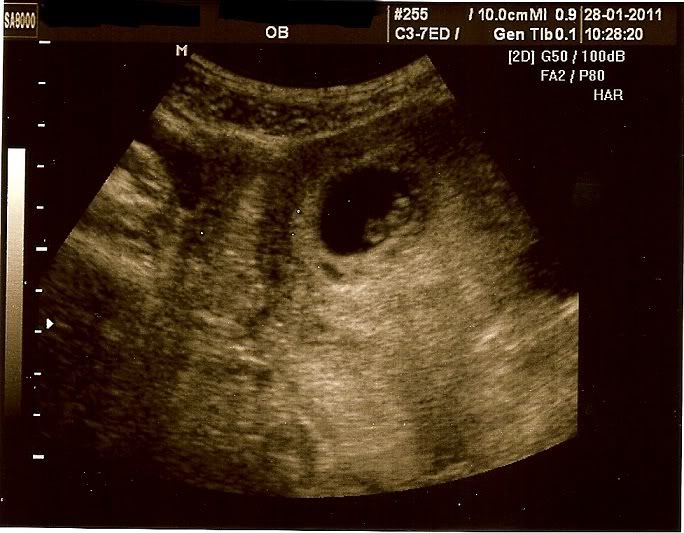

Ik ben heel erg blij. En toch ook nog een beetje ongerust, want het kindje was heel klein. De verloskundige kon het niet goed meten, maar ze schatte in dat het nu ongeveer 7 weken is in plaats van 8 weken.

17 februari krijg ik een termijnecho en dan kan ze het vast beter zien. Maar er zat tenminste wat! En het hartje klopte... en ik kon het ook even horen... wat een prachtig geluid!

Ik heb een foto meegekregen van de echo, en uiteraard even voor jullie gescand:

Prachtig he...